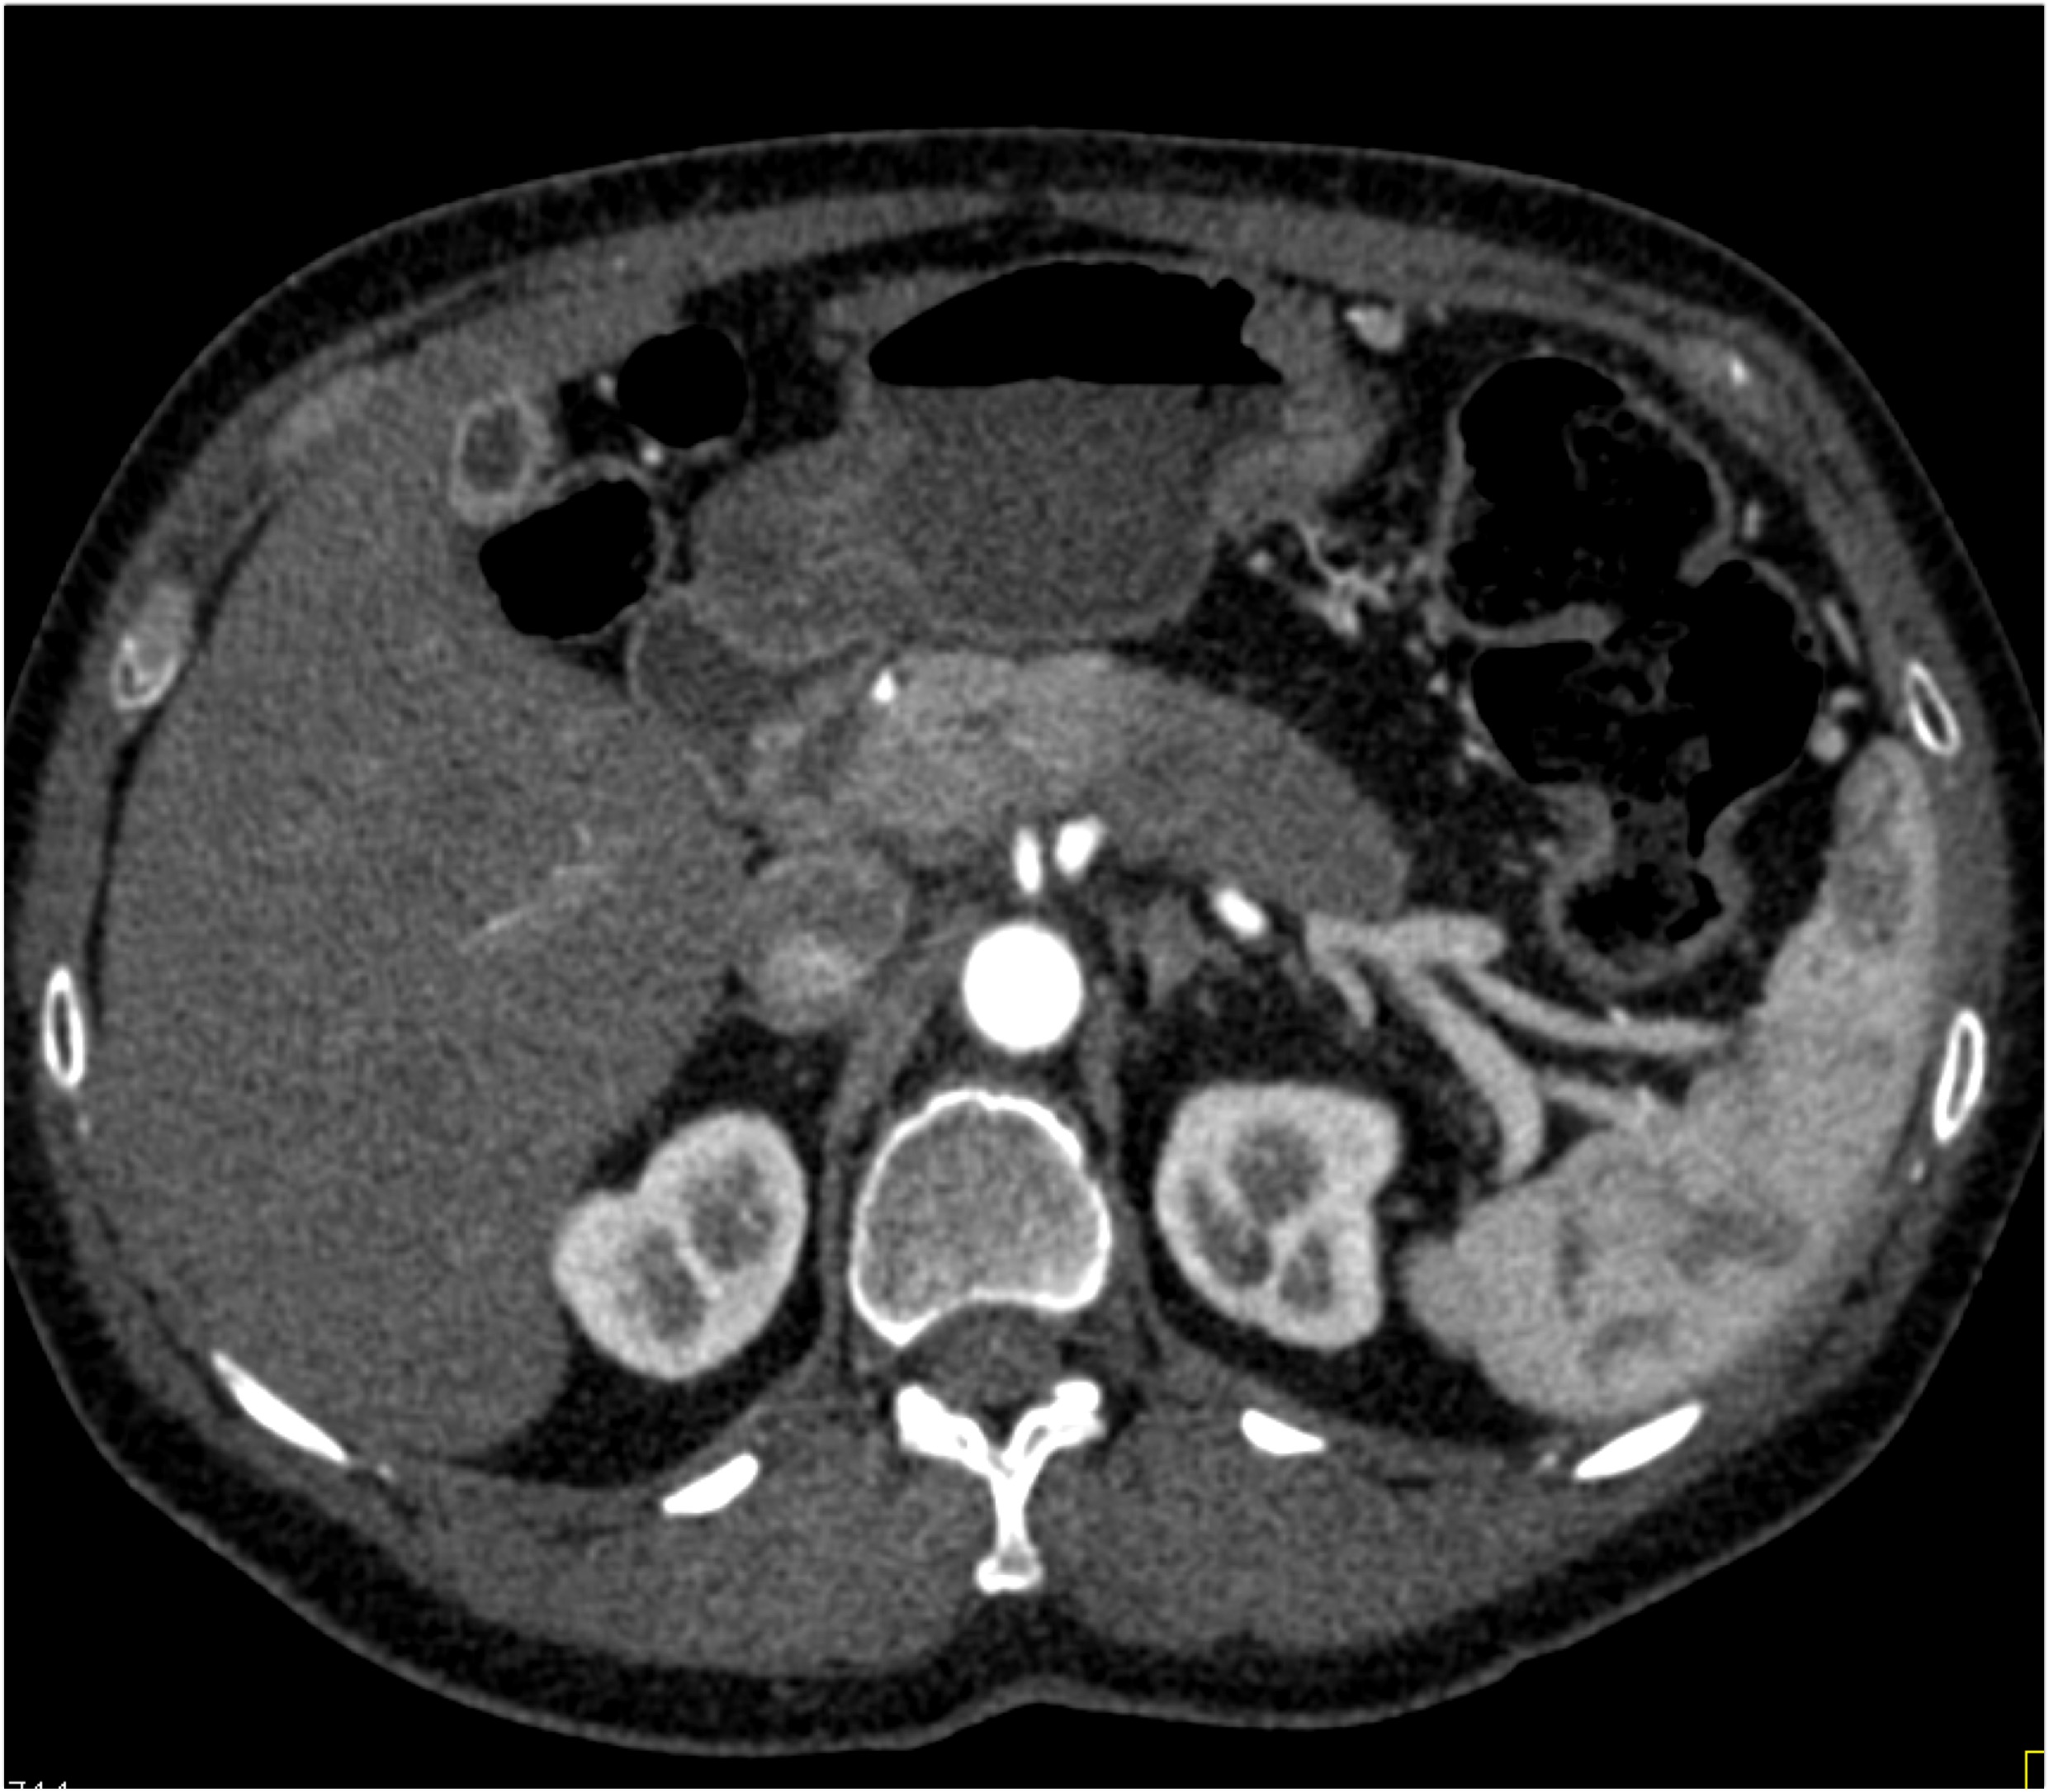

8) The most likely diagnosis in this case is?

clear cell renal cell carcinoma

large B-cell lymphoma

seminoma

renal abscess